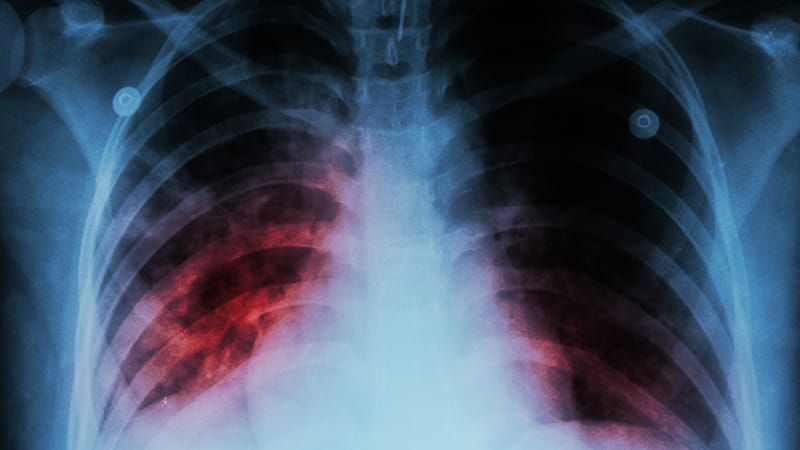

While for the past 30 years, the incidence of active tuberculosis (TB) in the US has been lower than the global incidence, untreated latent TB infection (LTBI) is thought to account for the majority of domestic infections. In fact, about 80% of US active TB cases may have progressed from LTBI that was untreated…